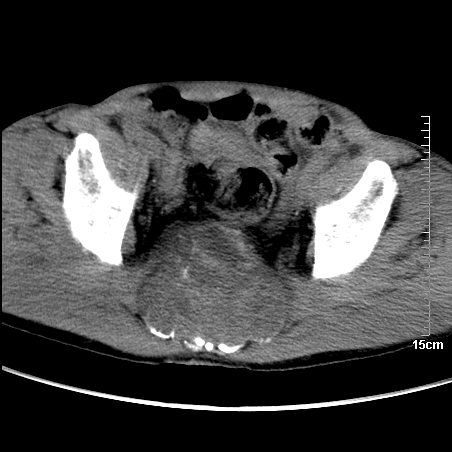

标题: CT16886:骶尾部占位:1.脊索瘤?2.巨细胞瘤?

平扫:

部分骶尾骨已被软组织密度的肿瘤所取代,同意“首先考虑脊索瘤,不除外转移瘤”的意见。

1、骶尾部巨大软组织肿块,部分骶尾骨以被软组织肿块代替,呈不规则侵蚀;病变突向盆腔内;增强扫描病变呈不均质强化;首先考虑脊索瘤。不支持的一点就是病变内无钙化。